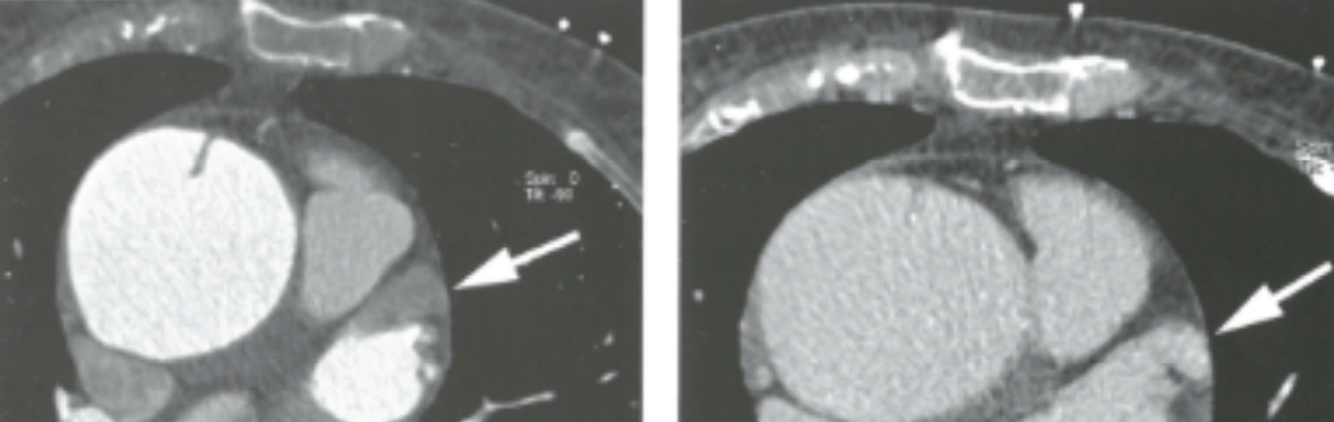

Describe the findings